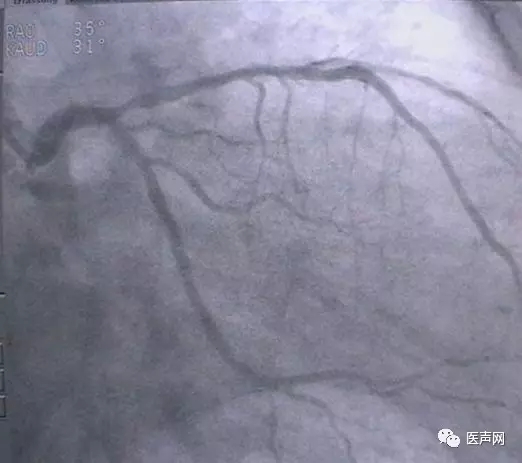

病例3:LAD中段90%狭窄

操作过程:JL4导引导管同轴性不好,支撑力不够,直接支架术(direct stent)有阻力,改用EBU 导引导管---植入TAXCOR 3.0×18mm DES.说明:导引导管的重要性。下图所示: